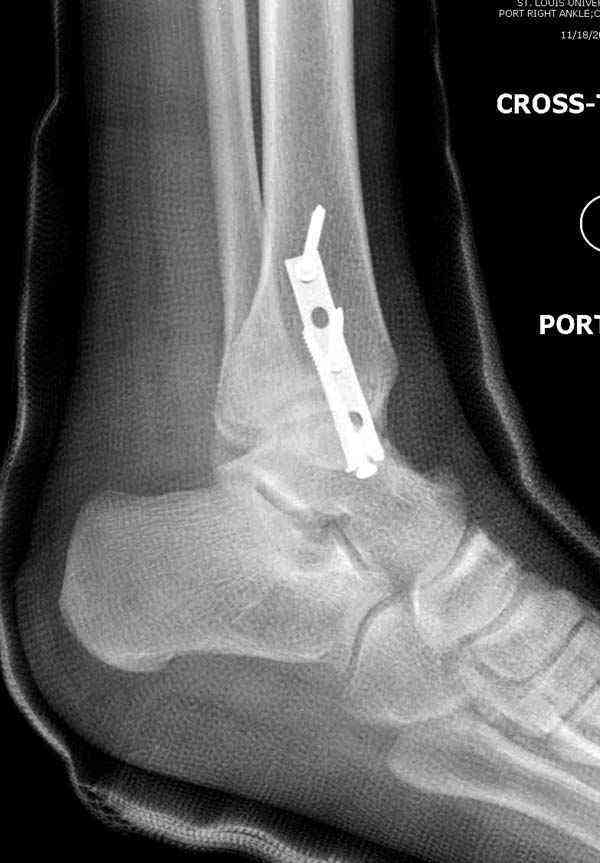

Во всех руководствах АО имеется описание техники применения низкопрофильных пластин 1/3 трубки, которые могут быть применены для фиксации наружной лодыжки. Фиксацию проводят кортикальными 3.5 мм шурупами, и если дистальная фиксация недостаточная, тогда усиливают конструкцию созданием hook plate. Сгибая конец пластины на последнем отверстии, внедряют его в дистальный отдел, и тем самым создается дополнительная фиксация.

Современные преконтурированные пластины не имеют таких недостатков, и разделяются на правые и левые, а также на латеральные и задние. Множественные дистальные шурупы 2.7 мм уменьшают подкожное раздражение, и такой имплант можно оставить на долгий срок без удаления.

Здесь несколько частных случаев: перелом голеностопа со сравнительными снимками и разрыв синдесмоза, а также медиальная Hook пластина.